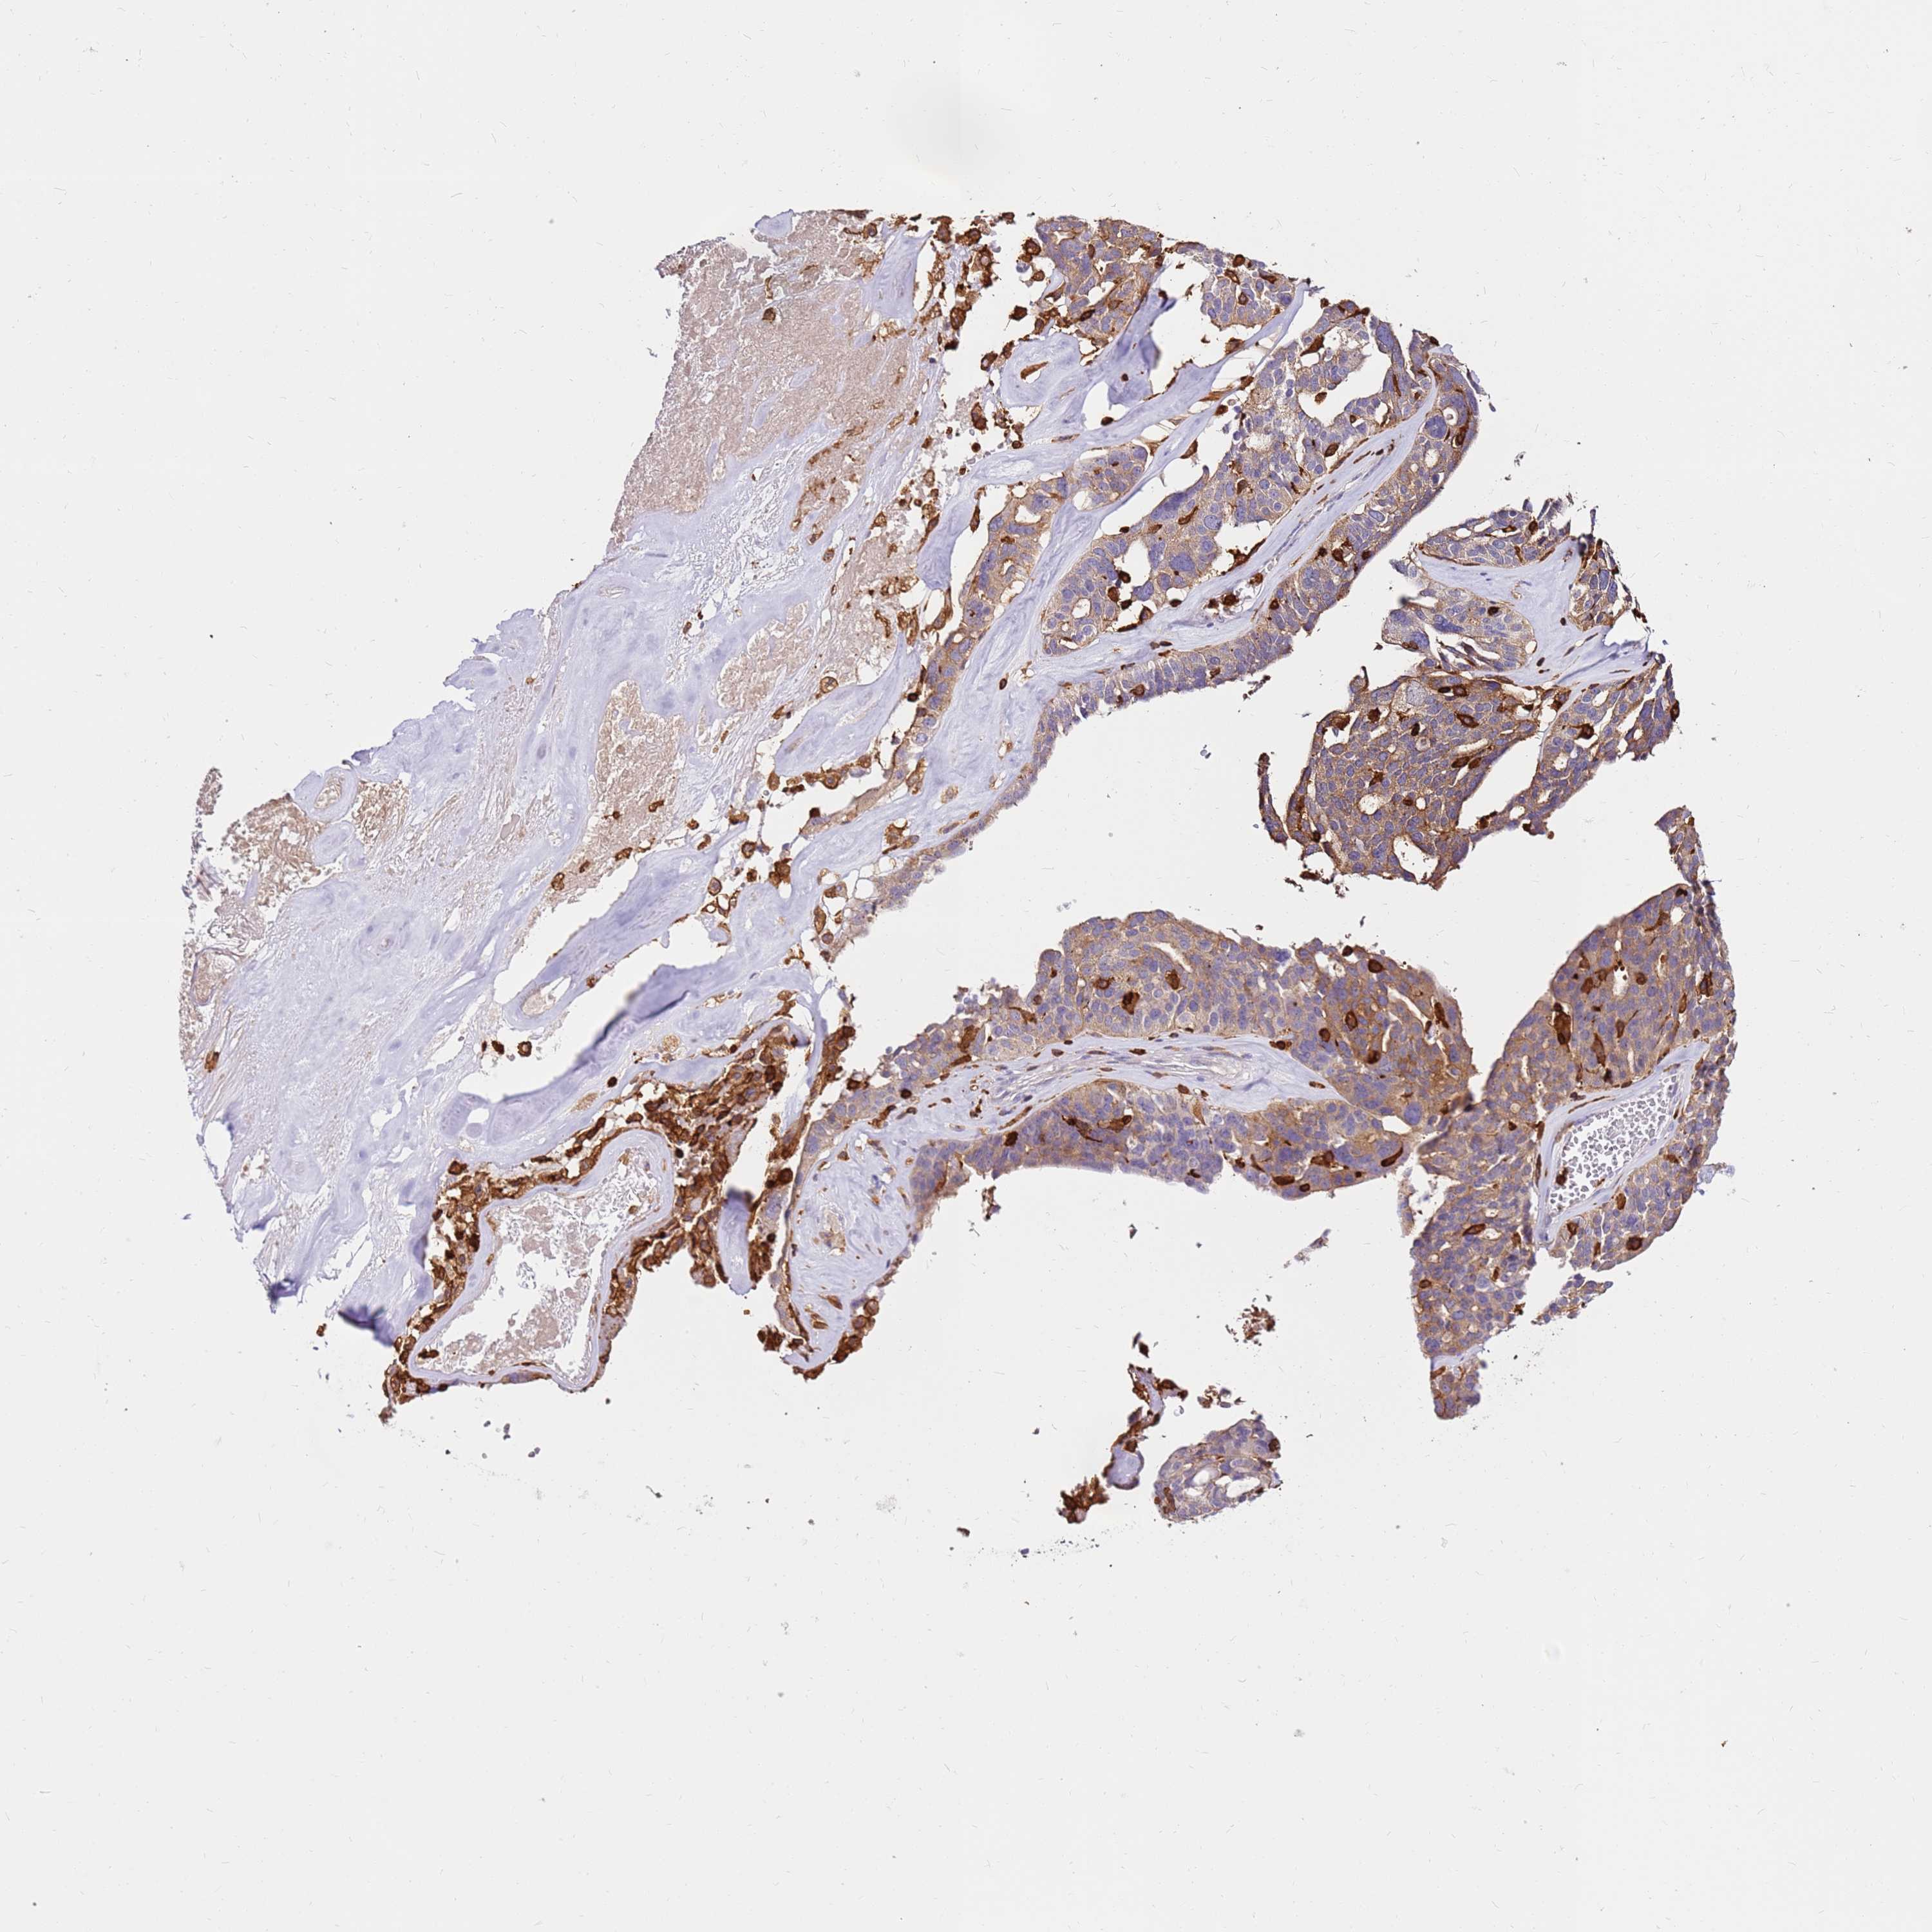

OVARIAN CANCER - Protein expressioni

A mouse-over function shows sample information and annotation data. Click on an image to view it in a full screen mode. Samples can be filtered based on level of antibody staining by selecting one or several of the following categories: high, medium, low and not detected. The assay and annotation is described here.

Note that samples used for immunohistochemistry by the Human Protein Atlas do not correspond to samples in the TCGA dataset.

Antibody stainingi

Antibody staining in the annotated cell types in the current human tissue is reported as not detected, low, medium, or high, based on conventional immunohistochemistry profiling in selected tissues. This score is based on the combination of the staining intensity and fraction of stained cells.

Each image is clickable and will lead to virtual microscopy that enables deeper exploration of all samples and also displays staining intensity scores, fraction scores and subcellular localization as well as patient and tissue information for each sample.

Antibody HPA051132

Antibody CAB046473

Cystadenocarcinoma, serous, NOS

Carcinoma, NOS

Cystadenocarcinoma, mucinous, NOS

Carcinoma, endometroid